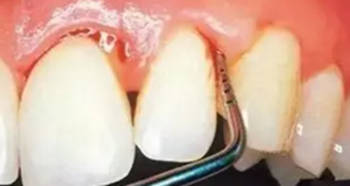

第一步:淺齲

當(dāng)我們身上有小黑點時,您毫不在意地說:“沒事的,沒感覺。”

牙醫(yī)說:“齲病是由以細菌為主的多因素導(dǎo)致的牙齒硬組織發(fā)生慢性進行性破壞的一種疾病。已經(jīng)開始淺齲即牙釉質(zhì)齲,需要做藥物治療或充填治療。